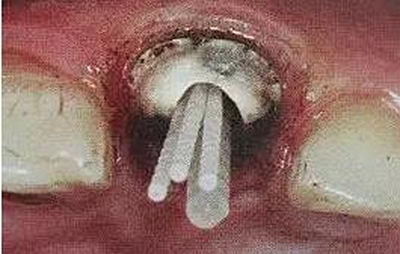

一般纖維樁使用數(shù)目要根據(jù)根管的粗細(xì)和牙體缺損范圍來(lái)設(shè)計(jì),像牙膠尖根充一樣,在主尖周?chē)梢苑胖幂o尖。

后牙一般按照牙體缺損范圍來(lái)設(shè)計(jì),一般2到4個(gè)足夠了。

在操作的過(guò)程中要注意無(wú)菌操作,保證纖維樁的無(wú)菌狀態(tài)。推薦將樹(shù)脂核堆好之后再截?cái)嗬w維樁,而不是截?cái)嗪笤僬辰印H缦聢D: